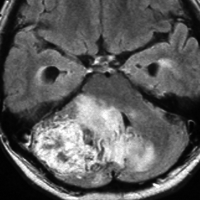

ものすごく難しい血管芽腫

これも血管芽腫です。おそらく小脳発生なのでしょうが,延髄の両側に強く癒着していて延髄の血管も腫瘍の中に入っていて,腫瘍血管には動脈瘤も合併していて破裂しました。この腫瘍を摘出するのは不可能にも思えましたが,無事にできました(下の写真)。患者さんも私もへとへとになりました。 でも,このような血管芽腫の手術はうまく行くとは限りません,手術不可能と考えた方がいいかもしれないと今でも思っています。手術すると決めればものすごく高いリスクを患者さんも外科医も背負うことになります。放射線治療をして治るサイズではないので他に治療法はありませんが (>_<) 大きな血管芽腫を手術する提案をされたら,少なくとも執刀医の経験数は尋ねましょう。